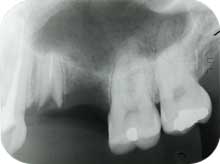

2.咬合治療の一環としての症例

咬合治療の一環としてインプラントが重要な位置づけとなる症例が多くあります。

![]() ![]() ![]() |